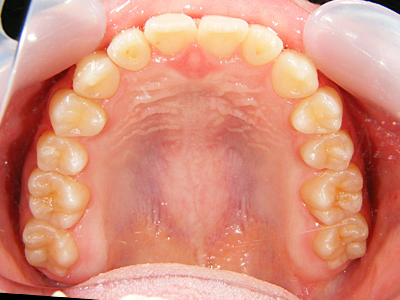

12. 術後上顎

術前と比較して前歯の翼状捻転の改善、上顎顎堤の拡大が認められます。

当然顔貌の変化も認められ、「ちょっと下顎が過成長なのかな?」と思った顔貌も改善しました。上顎の成長が止まる時期でしたが、少し手を加えるといわゆる成長曲線の範疇に戻ることをよく経験します。